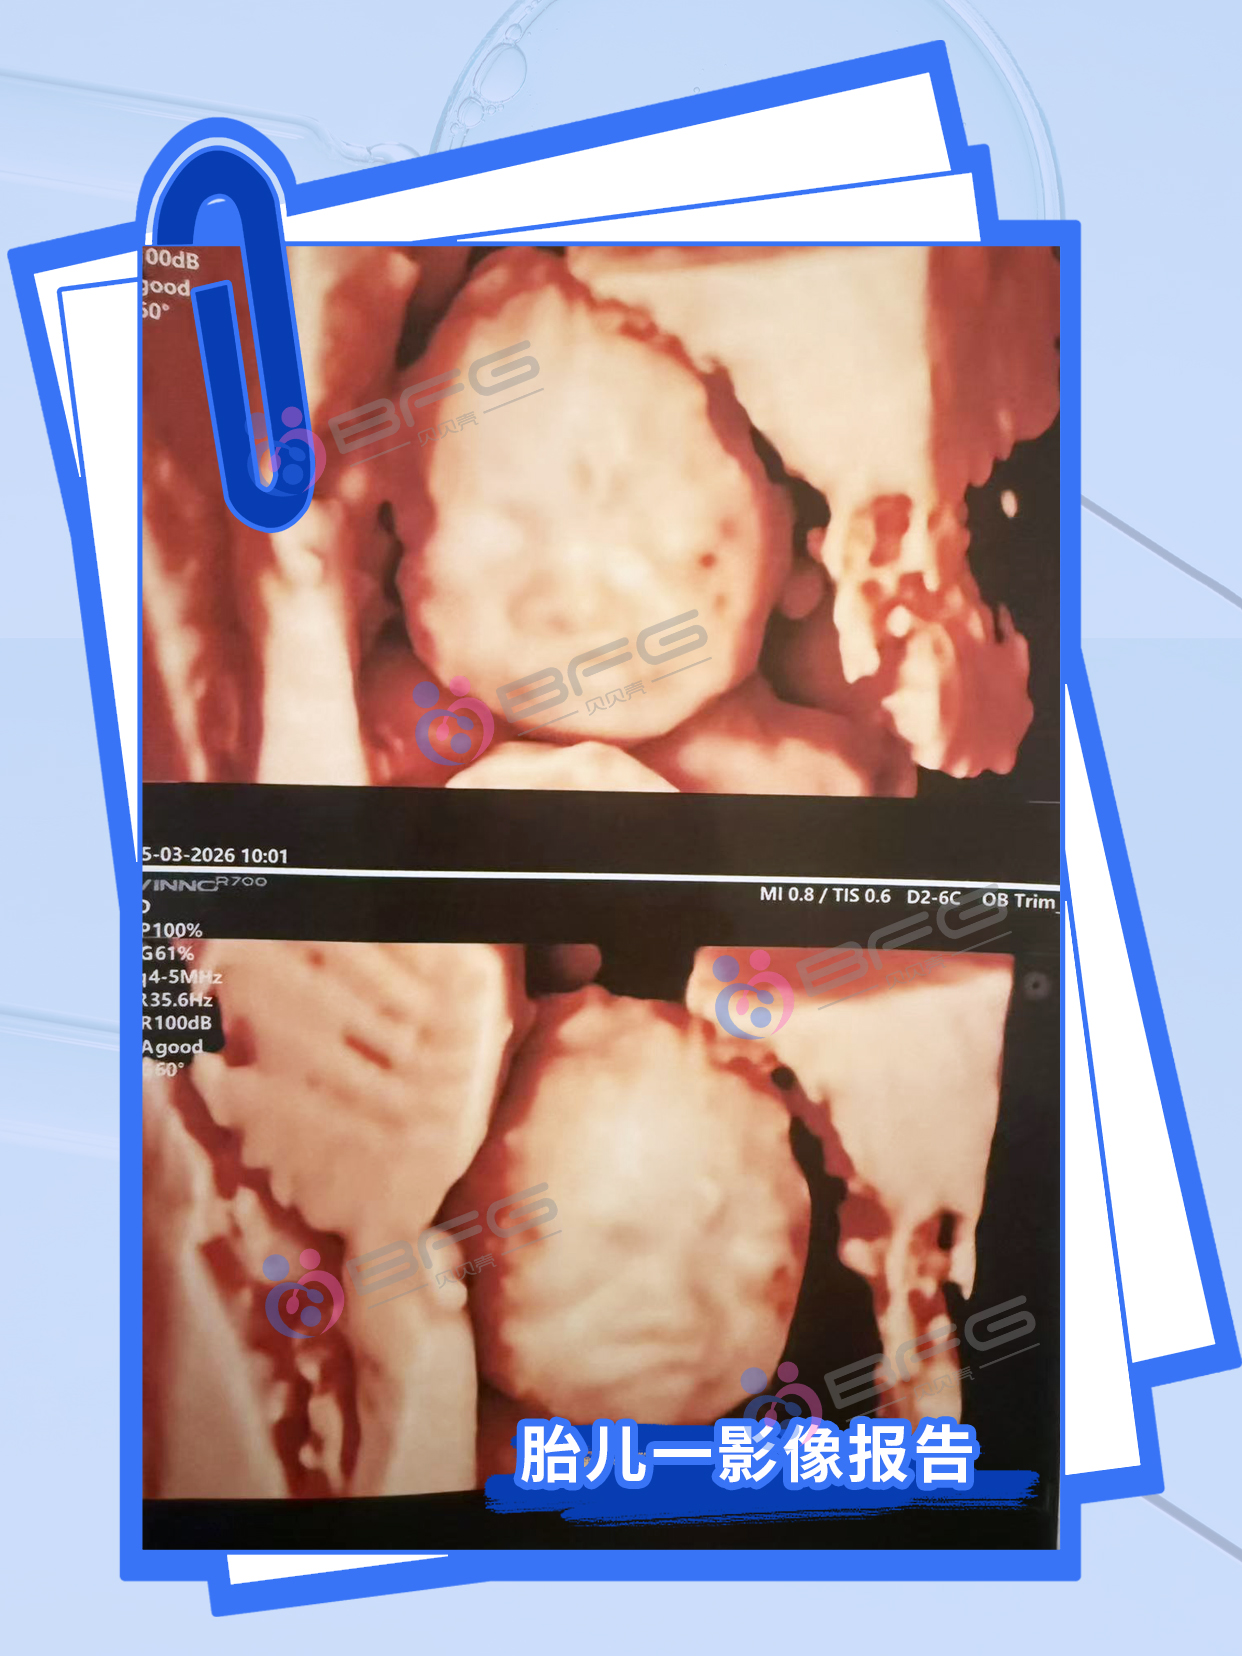

双胎24周,超声通关!两个小宝贝同步茁壮成长,各项指标棒棒哒~ 期待健康双倍惊喜!